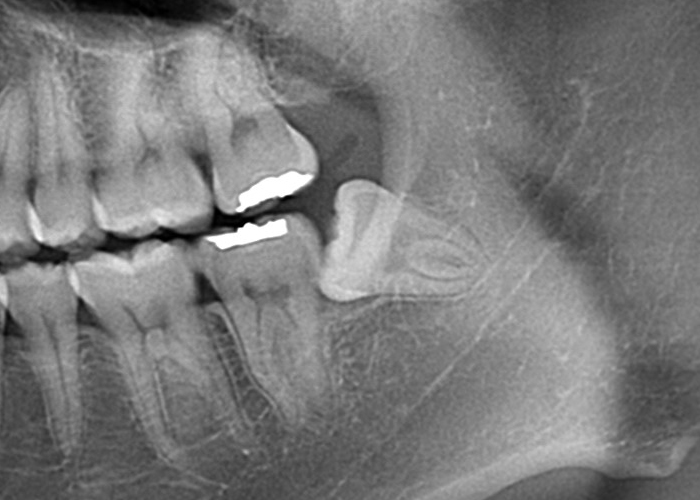

完全埋伏智歯(歯茎に完全に埋まっている)

完全埋伏とは、親知らずが完全に歯肉の下に完全に埋まっている状態を指します。

この場合、親知らずは通常、レントゲンやCTスキャンなどの画像検査でのみ確認できます。

完全埋伏の親知らずは、周囲の組織に直接的な問題を引き起こさない場合もありますが、将来的に問題を引き起こす可能性があります。

そのため、定期的な口腔検診や画像検査が重要です。